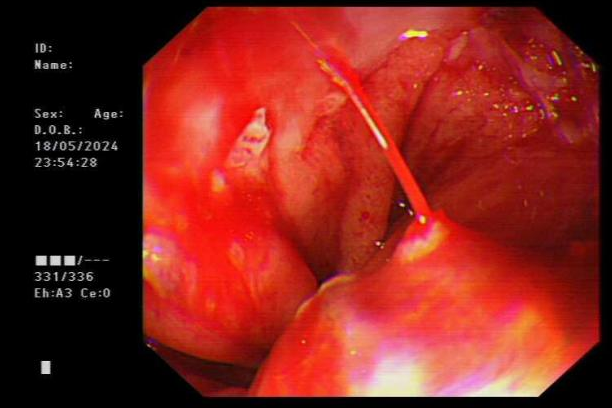

图片

食管贲门黏膜撕裂活动性渗血